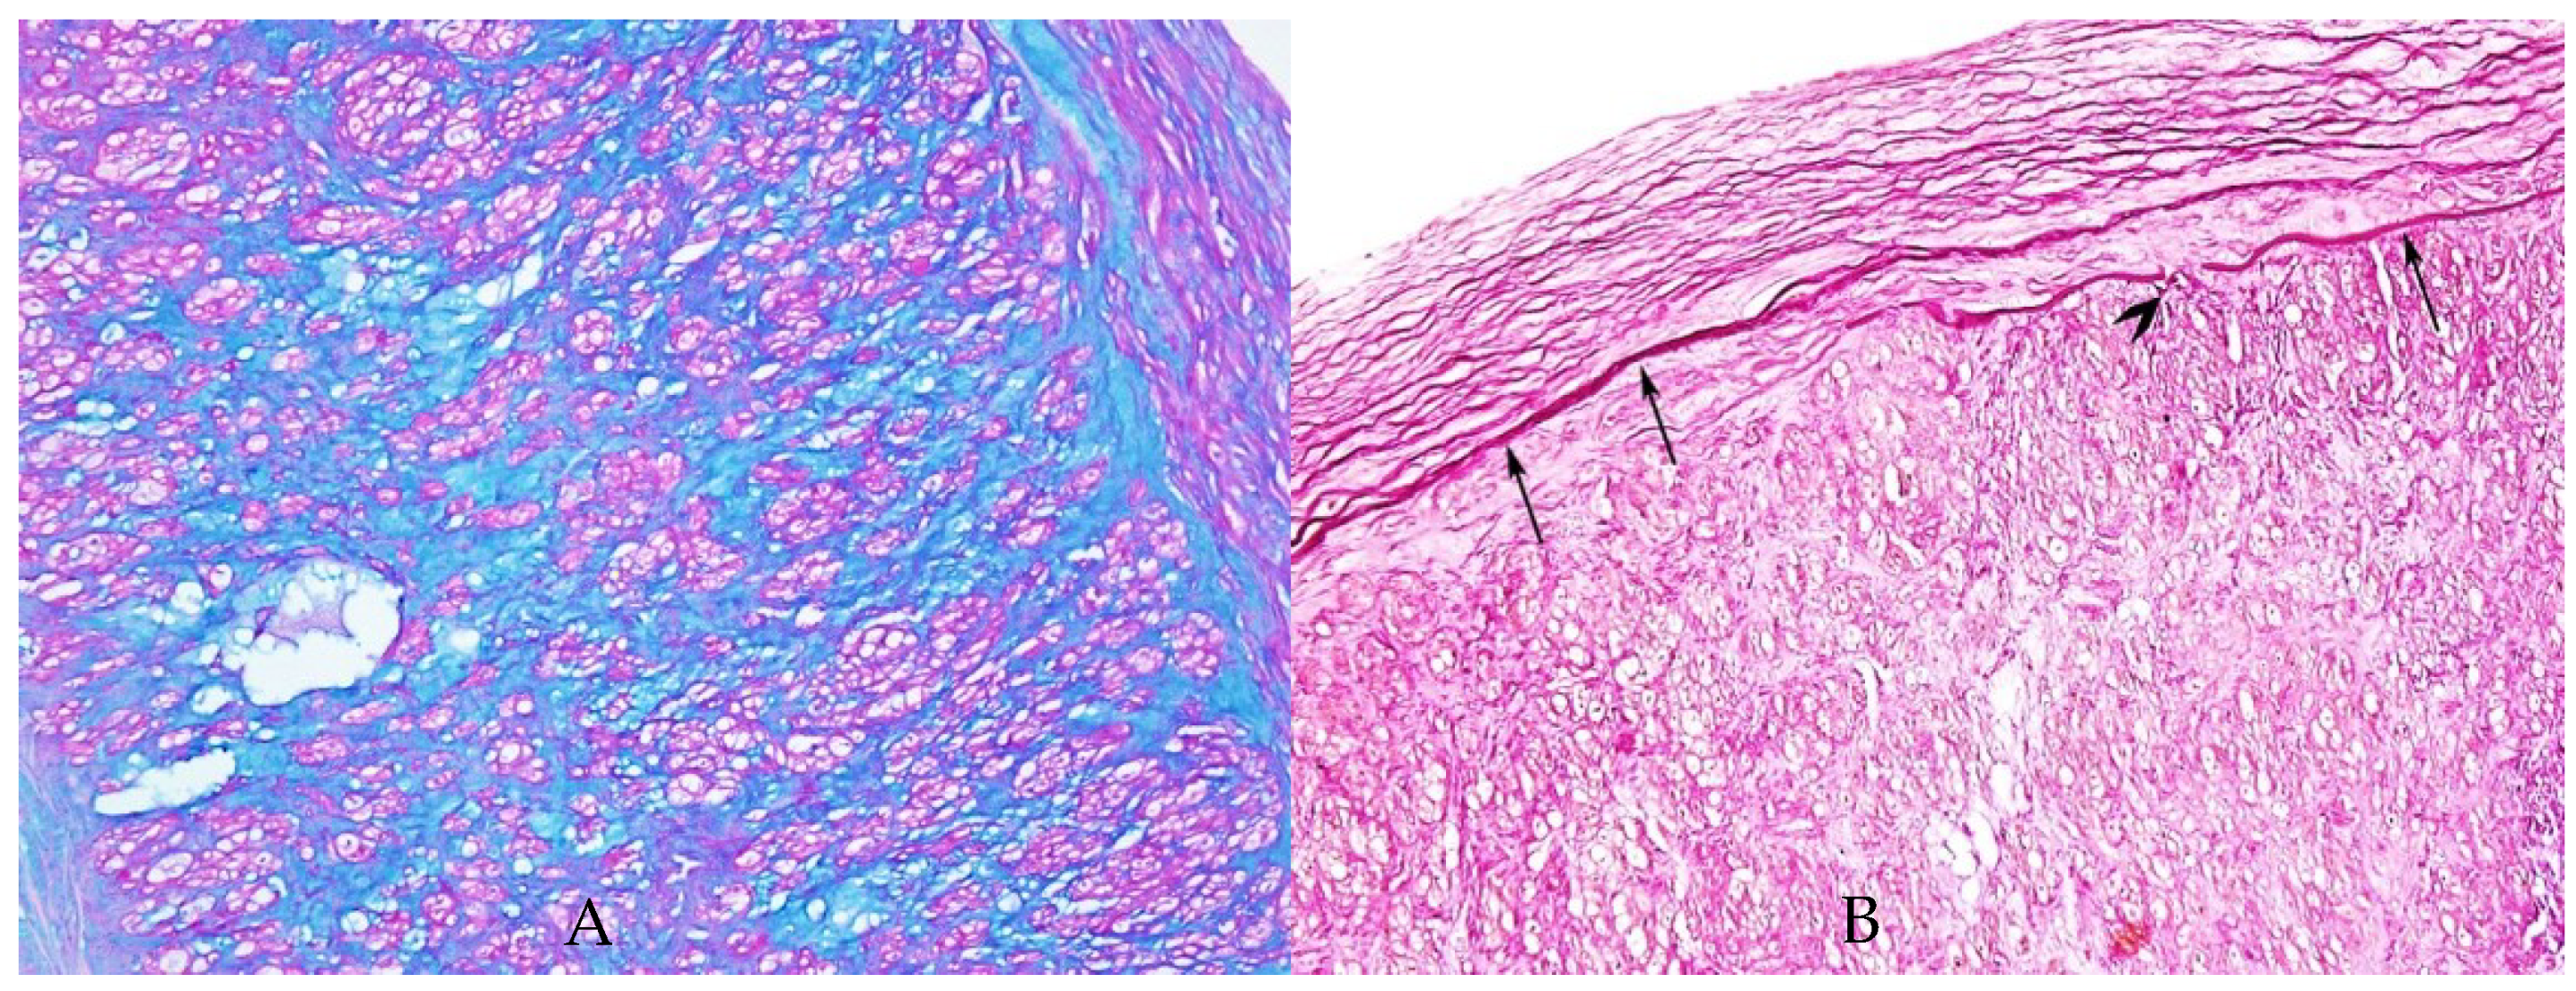

3. Results